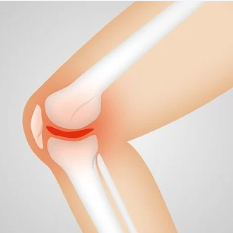

콜라겐의 효능 2. 관절 건강

콜라겐은 관절 연골의 주요 구성 성분 중 하나입니다. 연골은 뼈와 뼈 사이를 완충해주며, 관절 운동을 원활하게 합니다. 콜라겐 부족은 연골의 품질을 떨어뜨려 관절 건강에 부정적인 영향을 미칠 수 있습니다. 단순한 연령보다는 급격한 운동이나 부상으로 인한 연골 손상일 경우 콜라겐 섭취가 더욱 중요합니다. 관절 건강을 유지하기 위해 적극적으로 콜라겐을 섭취하는 것이 좋습니다.